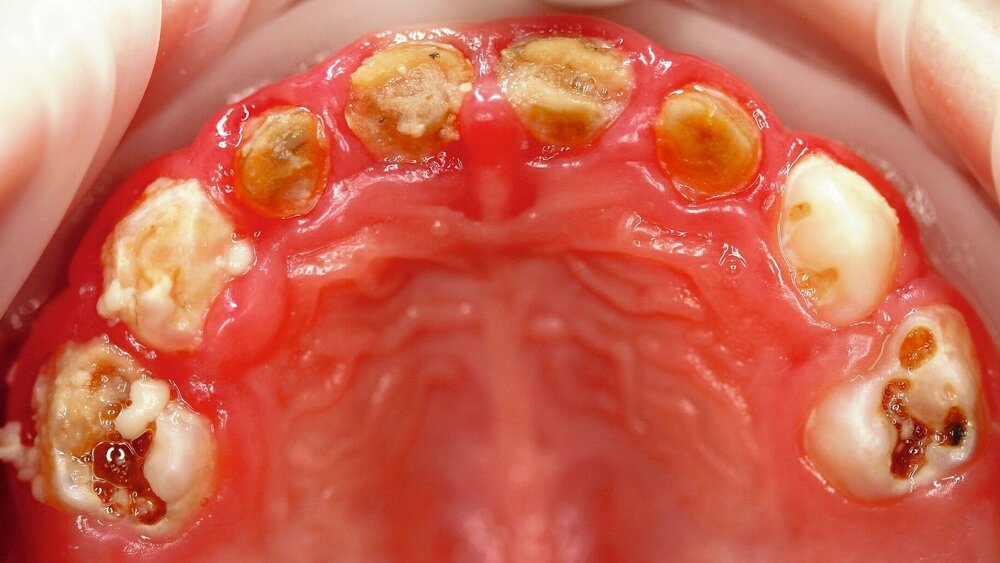

Im bleibenden Gebiss hat sich Deutschland bei den 12-Jährigen laut der kürzlich erschienen DAJ-Studie zur Gruppenprophylaxe [Team DAJ, 2017; siehe zm 6/2018, S. 40–49] einen internationalen Spitzenplatz bei der Kariesprävention erkämpft. Ein Trend, der sich bei den Erwachsenen fortsetzt [IDZ, 2016]. Im Milchgebiss sind jedoch dieselben Eltern und Zahnärzte in Gruppen- und Individualprophylaxe weit weniger erfolgreich. Dies ist an durchschnittlich drei bis vier kariösen Milchzähnen bei circa 14 Prozent der 3-Jährigen erkennbar, die an frühkindlicher Karies (Abbildung 1a) leiden, und erhöht sich kontinuierlich auf fast die Hälfte der Erstklässler. Schwere Formen der frühkindlichen Karies (≥ 4 dmft) sind bereits bei etwa 5 Prozent der 3-Jährigen vorzufinden [Team DAJ, 2017]. Daher lohnt es sich, die Präventionsstrukturen und Maßnahmen im Milchgebiss genauer zu beleuchten.